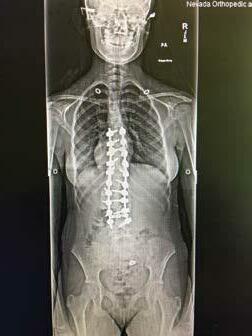

TOP 1% OR HIGHER ON NATIONAL EXAMS INCLUDING MOST RECENT BOARD RE-CERTIFICATION 30+ YEARS OF SPINE SURGERY EXPERIENCE DOUBLE BOARD-CERTIFIED 20+ YEARS AMERICAN BOARD ORTHOPEDIC SURGERY AMERICAN BOARD SPINE SURGERY PATRICK MCNULTY, MD F.A.B.O.S. • F.A.B.S.S. JOHNS HOPKINS FELLOWSHIP IN SPINE SURGERY 2 OFFICE LOCATIONS: 3012 South Durango Drive • Las Vegas, NV 89117 3175 Saint Rose Parkway, Ste 320 • Henderson, NV 89052 702-463-1424 • www.mcnultyspine.com • mcnultyteam@mcnultyspine.com LOWER BACK PAIN • NECK PAIN • SCIATICA • SCOLIOSIS• SPINAL STENOSIS SPINAL INJECTIONS • MINIMALLY INVASIVE SURGERY • KYPHOSIS • SPINAL RECONSTRUCTION MEDICOLEGAL EVALUATION/TREATMENT/EXAMINATIONS